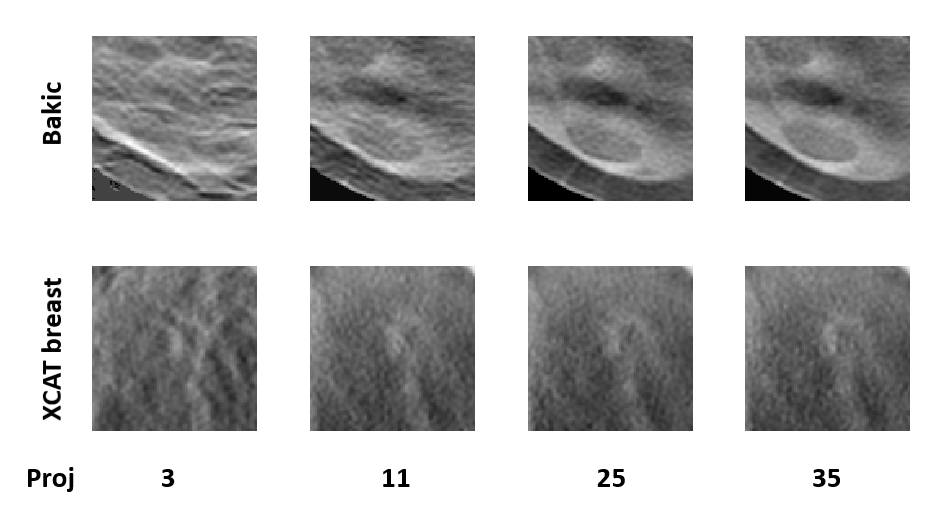

In our studies, each human observer was tasked with search and localization of a 3-mm lesion within the displayed DBT image slice (similar to the ones shown in fig 1). Figure 3 shows sample regions of DBT slices with lesion at the center of region to illustrate the changes in the visibility of the signal for varying number of projections in both types of phantom backgrounds. The signal is better visible in Bakic phantom background for the acquisition configuration of 35 projections, whereas the signal is better visible in XCAT breast background for the acquisitions of 11 to 35 projections. Figure 4 presents LROC plots for the three observers, for a sample acquisition of 35 projections over arc span, in both phantom backgrounds. The y-axis of the LROC represents the joint probability of correctly localizing a lesion in a case reported as positive. Therefore, the curve reaches up to the percentage of cases with correct lesion localization. The LROC AUC values above zero are considered as better than guessing as the likelihood of guessing the lesion’s location is zero. Figure 5 shows the average performance of the three observers in both Bakic and XCAT breast phantom images. Error bar lengths indicate twice the standard error of the three observers’ AUC values. We observed a greater improvement in performance up to 11 projections in XCAT breast phantom backgrounds and a steady performance thereafter. This corresponds to an arc sampling of approximately between adjacent projections for peak performance. In Bakic phantom backgrounds, observers’ performance improved up to 25 projections and required finer arc sampling of approximately to achieve peak performance. We also plotted the detection performance separately for 25% dense and 50% dense slices, where 25% dense indicates easy level of task difficulty while 50% dense indicates higher level of task difficulty. Regardless of phantom type, both levels of task difficulty show similar trends and suggest that optimization may not change with the task difficulty, which is in accordance with earlier observations by Zeng et al. zeng2017optimization and Mackenzie et al.mackenzie2021effect . We also noticed in figures 4 and 5 that observers had overall slightly lower performance in XCAT breast backgrounds than in Bakic backgrounds in particular for 25% dense images. This difference can not be attributed to phantom structures necessarily as the local densities in the region where lesions are inserted could also influence these LROC AUC. The magnitude of AUC values are less relevant in this particular study as only relative change in AUC values with changing system parameters (such a number of projection in this study) were used to deduce the final conclusions. The inter-observer agreement, quantified using the ICC, ranged from 0.92 to 0.95 with the average AUC values, suggesting a strong agreement between the observers.

This work evaluated the influence of variations between digital breast phantoms on DBT optimization and interpretation process for a small lesion localization task. Our results indicate that the phantoms should have adequate structures at spatial frequencies that are relevant for the signal size and the intended task for sufficient realism. We observed that optimal number of projections for peak detection performance could change with the structural complexity of the phantoms. In addition, we observed that the number of projections required to achieve maximum performance is smaller for XCAT breast phantoms than for Bakic phantoms. Our power spectrum analysis revealed that the complex structures in Bakic phantoms contribute to high frequencies while the high-frequency content of XCAT breast phantoms showed lower amplitudes. These high-frequency structures resulted in more aliasing artifacts in Bakic phantom backgrounds compared to XCAT breast phantom backgrounds under similar sparse sampling conditions. Hence, more projections were required to resolve these high-frequency structures in Bakic phantom backgrounds.